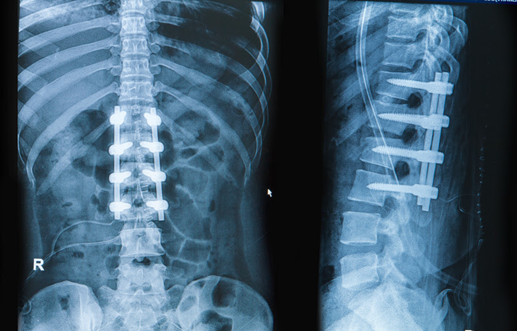

Cirugía de Columna

Servicios especializados para el diagnóstico, tratamiento y rehabilitación de patologías de la columna vertebral, utilizando tecnología de última generación y técnicas mínimamente invasivas reconocidas en centros de excelencia Internacionales

• Fusión vertebral asistida por navegación 3D y robótica.

• Tratamiento quirúrgico de escoliosis y deformidades en adultos y niños.